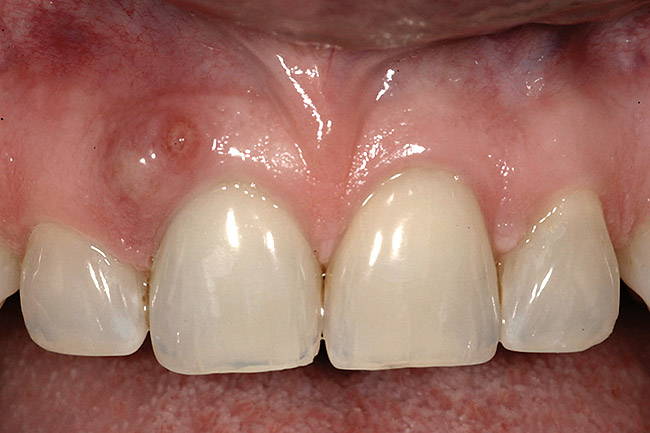

Figure 10  In these adjacent implants placed in the central and lateral positions, note the excellent interproximal bone but minimal interimplant distance.

Figure 10

Figure 12  At 6 months postinsertion, the papilla receded as bone was lost.

Figure 12

Figure 13  Twelve months after placement, soft tissue migrated apically as bone between the implants continued to resorb.

Figure 13